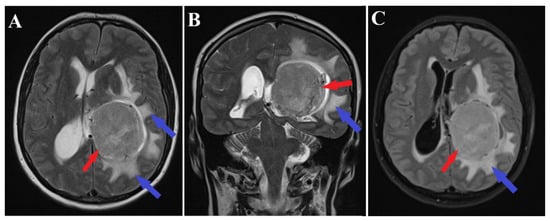

A brain MRI (i.e., multi-planar, multi-sequential brain MRI examination was performed on a General Electric 3T Signa Architect, Chicago, IL, USA) with contrast enhancement revealed an intraventricular tumor located in the body of the left lateral ventricle. The tumor presented as an ovoid, well-delineated mass with T1 hypointensity and T2 hyperintensity, measuring up to 60 mm in maximum diameter. It induced deformation of the left lateral ventricle. The tumor was associated with substantial digitiform edema, causing a shift in the midline structures and a potential risk of subfalcine herniation (Figure 1 and Figure 2).

Figure 1.

Preoperative MRI T1 and T1Gd sequence. Sagittal section of MRI T1 sequence (A) and axial section of MRI T1 Gd sequence (B), depicts an intraventricular mass into the left ventricle body (red arrows) with associated perilesional edema (blue arrow).